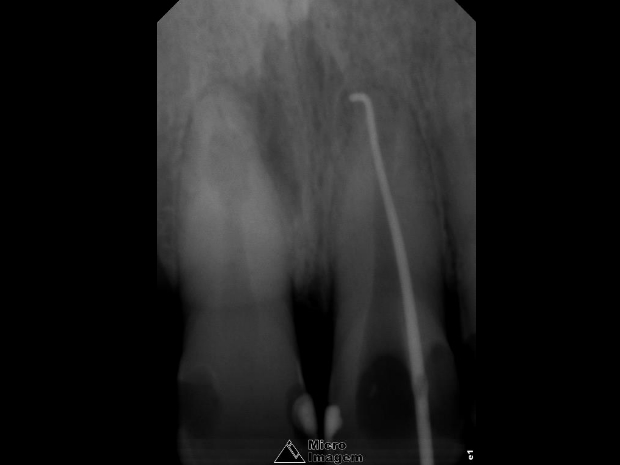

Após a abordagem inicial do paciente, o mesmo foi anestesiado e procedeu-se à confecção do isolamento absoluto. Posteriormente, o acesso coronário foi realizado, onde se constatou clinicamente a necrose pulpar de ambos os dentes. Foi realizada uma penetração desinfetante crown-down empregando como agente irrigador NaOCl a 5%, sendo a odontometria realizada pelo método radiográfico, devido a inviabilidade de emprego de um localizador foraminal nestas condições anatômicas, podendo influenciar em sua precisão (figura 4).

- Figura 4